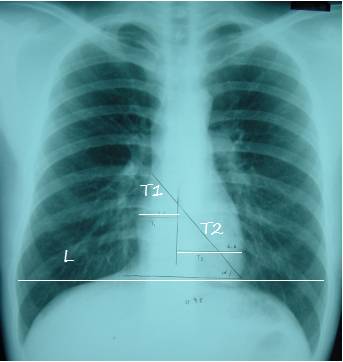

5. 心影位置及大小

T1:心脏最右缘至前正中线距离

T2: 心脏最左缘至前正中线距离

L:通过膈肌顶部至两侧胸廓内沿并平行于膈肌的线

心胸比=(T1+T2)/L

1.正常<=0.50

2. 轻度增大 0.51-0.55

3. 中度增大0.56-0.60

4. 重度增大>=0.60